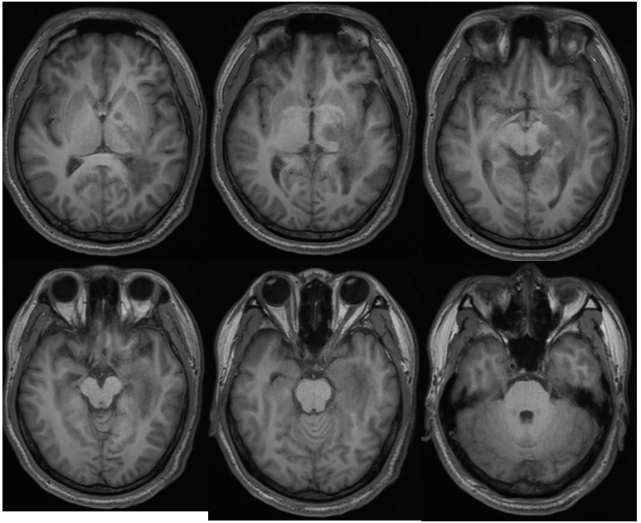

病例展示中枢神经系统脱髓鞘疾病是一组脑和脊髓以髓鞘破坏或髓鞘脱失

脱髓鞘疾病董会卿2020观点 董会卿 著 临床医学生活 新华书店正版图

16张mri影像征,助你"征"服中枢神经系统脱髓鞘疾病丨实战读片